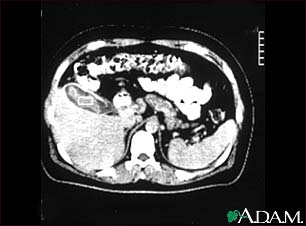

Cholecystitis, CT scan

This is a CT scan of the upper abdomen showing cholecystitis (gall stones).